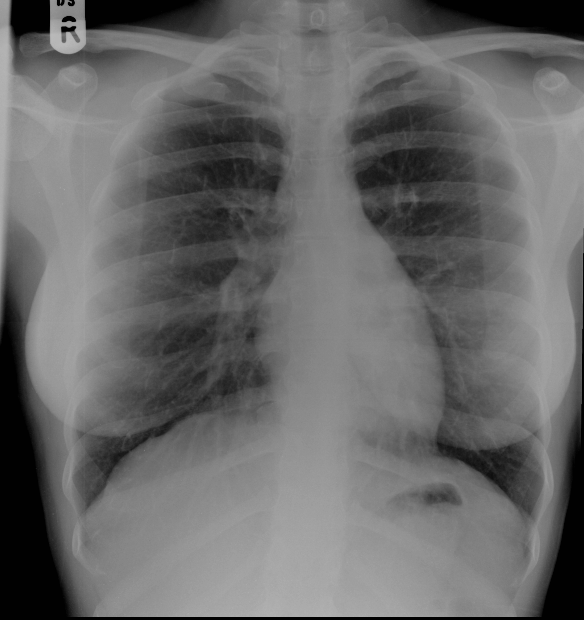

Abnormal ll col |

Abnormal Left upper lobe lung nodule |

Please check |

Correct |